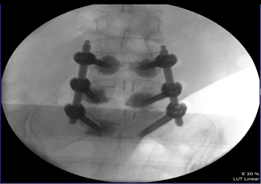

病例示範:

一位65歲女性因為第四腰椎至第一薦椎滑脫導致脊管狹窄及神經壓迫,經臨床影像學診斷證實後,需要進行脊椎減壓手術及骨融合植釘固定手術,到烏日林新醫院求診,手術以最新的免術前電腦斷層的電腦導航進行手術,手術後狀況良好,術後第三天就可以穿戴背架下床活動。

圖:脊椎電腦輔助手術導航